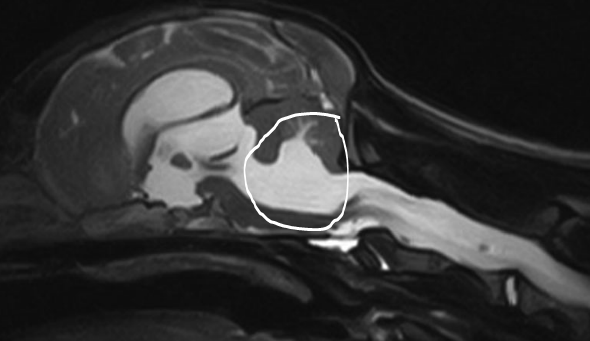

Differential for this?

Arachnoid diverticulum or cyst

Stenotic lateral apertures of the fourth ventricle

Obstruction by a non-contrast enhancing lesion (inflammatory, neoplasia, cholesterol granuloma